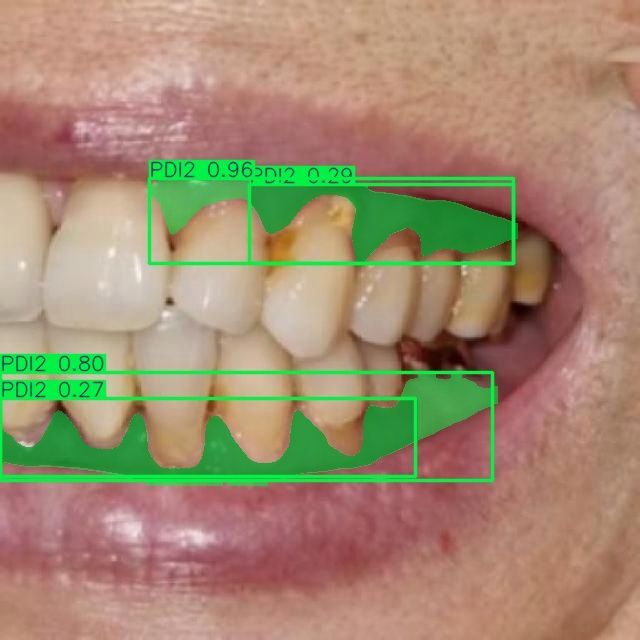

Мы проводим discovery-фазу для нашего клиента (стоматологическая клиника в Москве) и создали работающий прототип ИИ-сервиса, который автоматически сегментирует зубы и связанные патологии по 10 специализированным классам на стоматологических изображениях. Решение построено на Ultralytics YOLOv11-seg, обучено на пользовательском датасете и ускоряется на GPU (CUDA). Прототип уже демонстрирует корректную сегментацию и классификацию по классам кариеса, состояниям десен и показателям пародонта, что открывает путь к автоматизированной диагностике, системам поддержки клинических решений и оценке состояния зубов в реальном времени.

- Кариес: C1, C2, C3

- Пародонтальные индексы: PDI1, PDI2, PDI3